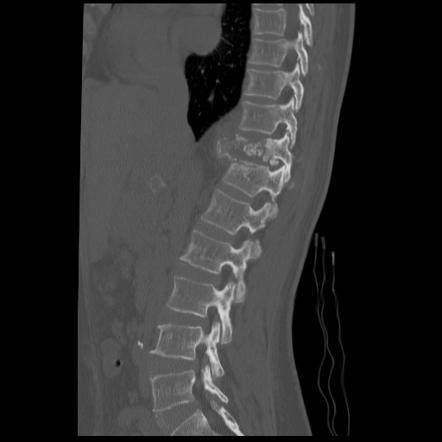

3. CT Scan: Provides detailed bony anatomy information like  end plates status, pedicle & posterior  bony elements integrity . It also assesses bone healing status in already under treatment patients.

- Repeat imaging studies (X-ray, MRI, or CT scan) at appropriate intervals to evaluate treatment effectiveness and detect any disease progression or complications.